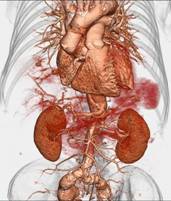

320排螺旋CT具备16cm宽覆盖探测器,实现动态容积扫描,360度的各向同性采集能力及[email protected]%密度分辨率的量子探测器,一次心跳全心脏采集,一圈扫描器官成像,一次检查完成多重任务,实现真正的动态容积体灌注及心脏、神经一站式检查;西门子Flash炫速CT扫描系统,具备两套同时旋转的X射线球管及探测器,实现了43cm/s的极快CT扫描速度和75 ms的时间分辨率,完成全胸扫描仅需0.6秒,使得患者做心脏扫描时无须食用β-受体阻滞药,亦无须屏气,并可实现低于1mSv的超低辐射剂量,配置第二代双能量、宽151级纯化能谱,组织鉴别能力进一步提高,可开展多达10余种双能量成像应用。

头颅一站式检查:320排容积CT覆盖范围达16cm,球管旋转一周可以覆盖整个脑组织,获得全脑0.5mm层厚各向同性全脑信息。一次扫描可以获得平扫容积图像、以时间为序列全脑动态3D-CTA图像(包括纯动、静脉期成像)及全脑灌注图像。一次检查即可排除脑出血、动脉瘤、动脉狭窄、梗塞、脑实质供血异常等多种病变及进行脑卒中筛查。